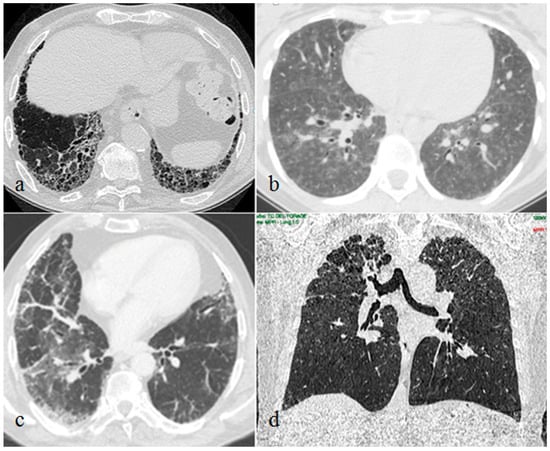

Furthermore, we reported the typical CT findings of the ILDs detected in our patients. UIP radiological features were subpleural and basal predominant honeycombing or reticulation with peripheral traction bronchiolectasis. NSIP was mainly characterized by bilateral patchy areas of ground-glass attenuation with basilar distribution and relative immediate subpleural sparing. HP typical radiological findings were diffuse with possible basal sparing ill-defined centrilobular nodules and/or air trapping associated with ground glass opacities and/or mosaic attenuation with or without fibrosis. PPFE CT images showed upper lobes predominant pleural and subpleural thickening with a reticular pattern, with possible associated upper lobes volume reduction and traction bronchiectasis.

The 10 lung biopsies performed confirmed the diagnosis suspected by the corresponding chest CT patterns. Seven patients showed NSIP, one patient showed PPFE, one patient showed HP and one patient showed early UIP pattern (Figure 2).

Figure 2.

Interstitial lung disease patterns in patients with plaque psoriasis: usual interstitial pneumonia (a), hypersensitivity pneumonitis (b), nonspecific interstitial pneumonia (c), pleuropulmonary fibroelastosis (d).